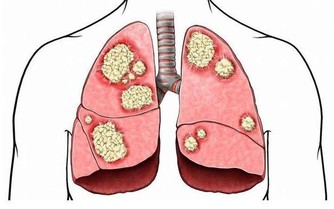

只見小於滿身滿臉的紅斑,上面有丘疹一樣的凸起,不少皮膚薄而脆弱,呈魚鱗狀,多處皸裂,皮損處甚至出漿出血。

看樣子還是典型的濕疹,但是大多數人長濕疹可能只是局部長一些,小於則是全身幾乎沒一塊好皮肉,為什麼會這麼嚴重?

壓力一大,休息不好,或是雜七雜八的東西吃多了,季節交替時,手肘內側、指縫、關節處等多摩擦的部位便會起紅色斑塊的丘疹,瘙癢難忍,越是抓撓便越嚴重,吃藥擦藥能控制住,但下一個輪迴便再度復發……

有些濕疹產生皮損,皮損痊癒後又會留下色素沉澱,影響肌膚美觀。